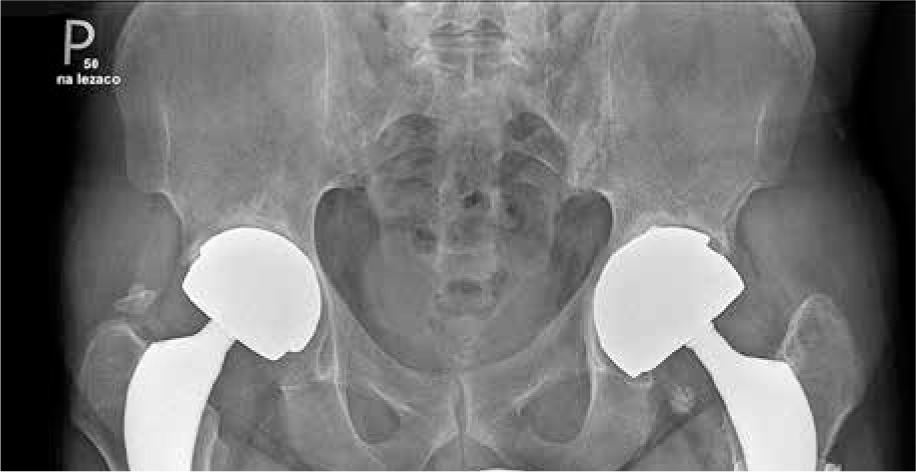

Fig. 2

X-ray of hands showing juxta-articular osteoporosis and inflammatory cysts. No erosions and joint space narrowing. Sharp/van der Heijde score = 0. Juxta-articular osteoporosis is a typical finding in hand X-ray in RA but rare in AS

Here, we describe a case of a 52-year-old man with long-standing ankylosing spondylitis (AS) with bilateral ankylosis of the sacroiliac joints, grade IV according to modified New York criteria (Fig. 1) with a history of peptic ulcer disease and no other comorbidities who developed seropositive rheumatoid arthritis (RA). The diagnosis of AS was made in 2006 and was based on a combination of inflammatory back pain, X-ray of the sacroiliac joints (bilateral grade III sacroiliitis at the time of diagnosis) and the presence of HLA-B27. He did not present peripheral arthritis, enthesitis, uveitis or psoriasis. At the time of diagnosis, inflammatory indicators were increased: C-reactive protein (CRP) 9.8 mg/l (normal value [NV] < 5 mg/l), erythrocyte sedimentation rate (ESR) 48 mm/h (NV < 12 mm/h]) but rheumatoid factor (RF) and anti-citrullinated peptides antibodies (ACPA) were absent. Baseline disease activity measured with Bath Ankylosing Spondylitis Disease Activity Index (BASDAI) was high: 8.6. Initially, the patient was treated with non-steroidal anti-inflammatory drugs (NSAIDs) for 6 years. Since NSAIDs ceased to control the disease activity in 2012, etanercept was introduced. He had undergone left (2013) and right (2014) hip arthroplasty due to severe secondary coxarthrosis in the course of AS. Because of worsening of spinal pain and stiffness, significant deterioration in mobility, and persistent systemic inflammation (ESR 52 mm/h, CRP 102 mg/l) etanercept was replaced with secukinumab in January 2020. In February 2020, after two doses of secukinumab, the patient was admitted to the tertiary rheumatology center with acute symmetric polyarthritis of new-onset involving shoulders, elbows, wrists, small joints of the hands, feet, and knees with pain scored 10/10 on the Visual Analogue Scale (VAS). Inflammatory indicators were increased: CRP 35 mg/l, ESR 73 mm/h. X-rays of the hands and feet did not reveal abnormalities. Ultrasound of the joints revealed (according to the OMERACT recommendations): GS = 1, PD = 1 bilaterally in the wrist joints, GS = 1 + effusion, PD = 0 (left hand III PIP); tenosynovitis in the fourth extensor compartment of the right hand (GS = 1 + effusion, PD = 0). Systemic steroid therapy was started and NSAIDs were maintained, resulting in a transient clinical improvement. At 2 months of follow-up polyarthritis with symmetric involvement of the wrists was still present. Autoantibodies were detected: ACPA 500 IU/ml (NV < 8), RF 379 IU/ml (NV < 15). Therefore, the patient was diagnosed with RA according to the ACR/EULAR 2010 criteria [1]. Treatment with the JAK inhibitor tofacitinib was initiated in July 2021. Despite treatment, symmetric polyarthritis of the hands persisted. Follow-up X-rays of the hands showed juxta-articular osteoporosis and inflammatory cysts in the joints that were most affected by ultrasound (Fig. 2). In December 2021 tofacitinib was switched to anti-interleukin (IL)-6 tocilizumab, which caused substantial clinical improvement and allowed remission of RA along with sustained remission of AS. Treatment modifications and disease activity are presented in Table 1. Comparison of RA and AS diagnosis and treatment is presented in Table 2. After 18 months of tocilizumab treatment, both RA and AS remain in remission (DAS-28 1.2, BASDAI 2.0, ESR 1 mm/h, CRP 1 mg/l).